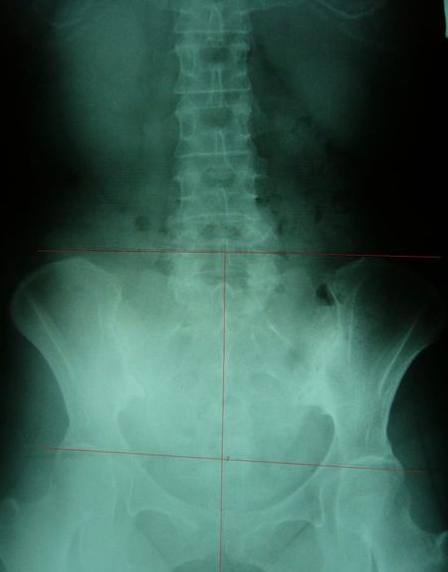

案例B:左图调理前骨盆严重歪斜左右极不对称 ;右图调理后骨盆歪斜改善骨盆圈呈现对称心型圆弧

一般最常见到骨盆歪斜的案例包括产后骨盆不正、车祸、撞击、跌倒、姿势不良…等等造成。骨盆歪斜的典型症状包括腰部、髋臀部、腿、膝部疼痛。列举三个自在美国取得脊医执照以来曾经处理过骨盆歪斜相当明显的案例。都是骨盆部位曾经遭受撞击。案例A是超过十年以上的陈年车祸旧伤、另一案例B是急性摔伤(两天内)的案例。两者的X光片都依照美国脊医X摄影方式采站姿摄影评价。借此同时评价骨盆在重力(gravity)影响下的反应。也可以泯除躺歪斜摄影而造成图像不正的情况。最简单的评价要点包括骨盆高低边?中线是否穿越耻骨联合?左右两边是否对称?我简单的几条线一画,相信连外行人也可以看出明显的骨盆歪斜的情况。案例A属陈旧性伤害在调理约两个月后明显降低腰臀腿部的不舒服。而案例B属急性伤害,案例B在调理近三周后骨盆疼痛由原先的持续疼痛降低为完全不痛。之后的骨盆X光摄影重新评价也显示骨盆旋转的问题大幅改善。